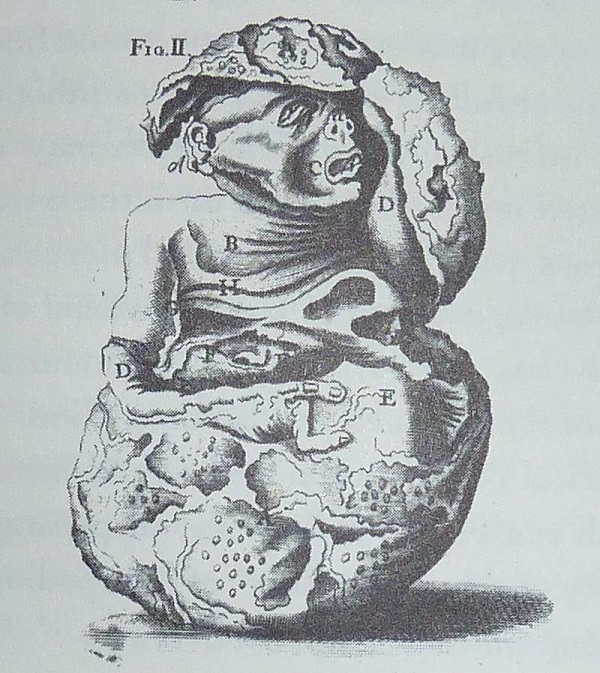

外科医生纪录的桑斯怪胎

这里面竟是一个蜷缩着的女胎,连头发纹理、牙齿以及未闭合的囟门都清晰可见。

她的头部略微朝左倾斜,并由左臂支撑。

其右臂则向肚脐位置延伸,半截手臂末入腹中。

在这之后,其中一名外科医生,便保留这了具女婴尸体。

他将此写成医学报道,并将女婴多次展览,最后卖给了商人。